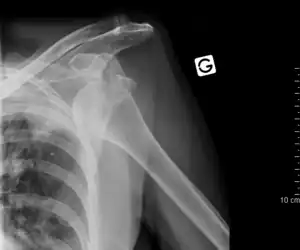

Luxation antérieure sous-coracoïdienne de l'épaule gauche.